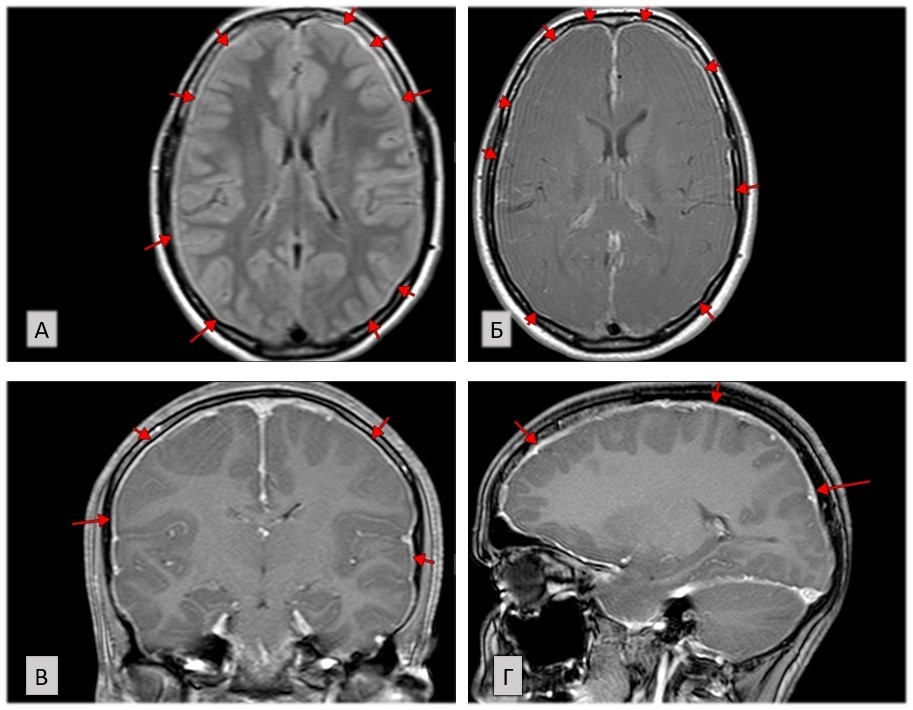

При проведении МР-исследования головного мозга с контрастным усилением выявлено:

1. Твердая мозговая оболочка диффузно утолщена, повышенного сигнала в режиме Flair, интенсивно накапливает контраст (рис.1).

Рис. 1. Утолщение ТМО и повышение МР-сигнала в режиме Flair (А), диффузное усиление утолщенной ТМО при в/в контрастировании (Б-Г), (авторское изображение).

Подобные изменения ТМО на МР-изображениях могут быть проявлением изменений воспалительного характера (пахименингита), однако в анамнезе данных за инфекционный процесс нет, и при дальнейшей оценке МР-изображений выявлены другие признаки, относящиеся к критериям внутричерепной гипотензии.